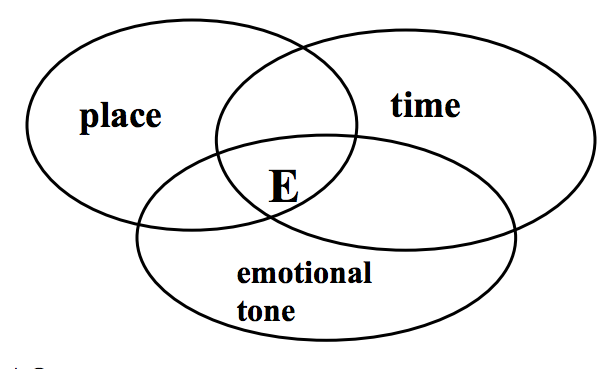

Describe episodic memory?

Autobiographical

Events in a personal context, including place, time and emotional tone